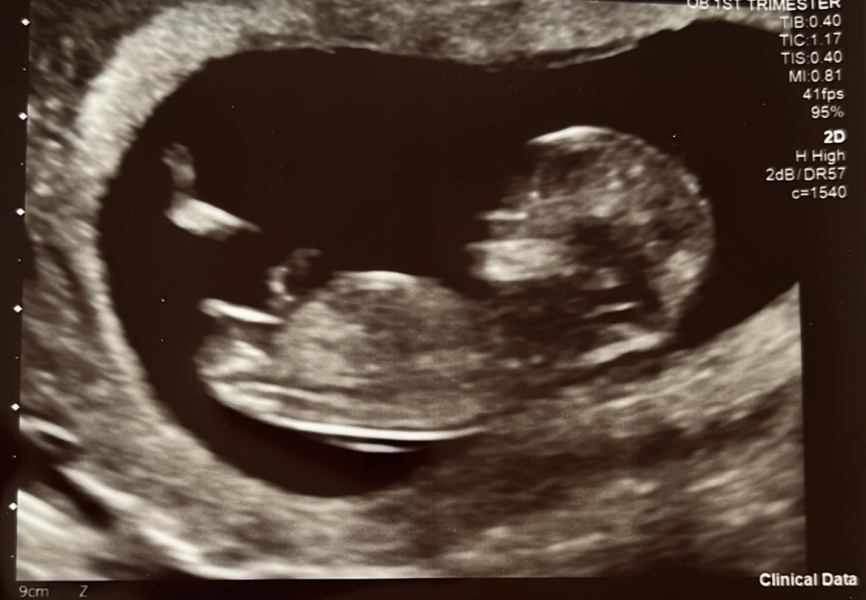

Hiya ladies, I'm new to mums net. I'm 13 weeks 4 days and I done the nub theory last week on gender experts. They done it based on the skull. I have no clue about it all really.. I just saw it as a bit of fun. Can anyone tell me what you think from my scan please? Thank you 😘

Nub theory prediction wrong?

ChristmasAtHogwarts · 18/09/2023 06:51

@Jamiexx boy x

@Jamiexx id go with boy!

Jamiexx · 18/09/2023 10:21

Thank you! The gender experts said girl by the skull, but from what pictures I have looked at of the nub theory then it looks like a boy to me too! I've been thinking it's a boy anyway. I'll have a very happy son if it's a boy! this baby was a massive surprise I have only 1 child a 15 year old. I always really wanted more but I had loads of complications for10 years in my belly following a serious car accident so having another baby had never been the right time, I just made peace with only having one and surprise! So it really doesn't matter to me if it's a boy or a girl as long as it's ok and I think my son will melt either way 🤣 xxx